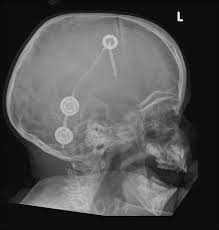

Normal Shunt Series Radiology Case Radiopaedia Org

Radiologic Identification Of Vp Shunt Valves And Adjustment Pediatric Neurosurgery Leipzig

Vp shunt x ray positioning. The shunt series is a set of radiographic images performed to assess the location and integrity of a ventriculoperitoneal shunt. In the context of hydrocephalus there are a multitude of therapeutic options that can be explored in order to improve patient outcomes. The external portion of the catheter is connected to a valve that regulates the flow of csf based on a preset pressure.

Programmable csf shunt valves. Shunt series for vp shunt x ray guideline. Indications departmental protocols will vary but the overall goal is to image the shunt in its entirety to assess.